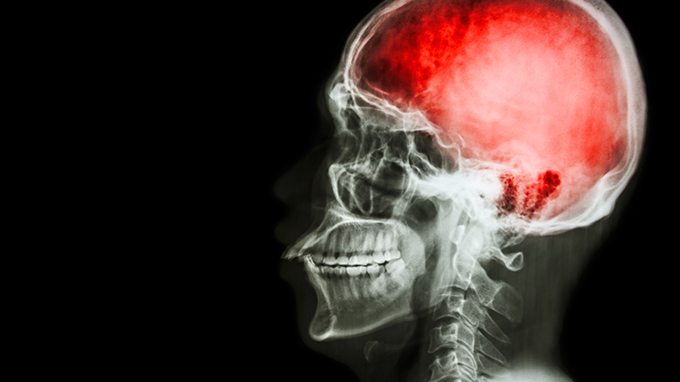

急性脑梗死治疗指南 如何诊断急性脑梗死

一、急性脑梗死治疗指南1.溶栓治疗也就是说,发病后3~6小时内进行。静脉给药溶栓或动脉给药溶栓在临床实践中没有得到广泛的应用。常用药物有尿激酶和纤溶酶原激活剂(t-PA)。颅内出血是溶栓治疗的主要危险性和副作用,心源性栓塞患者脑出血的几率较高。2.一般治疗①调节血压:脑梗死时应谨慎使用降压药,如血压为150~160/1..